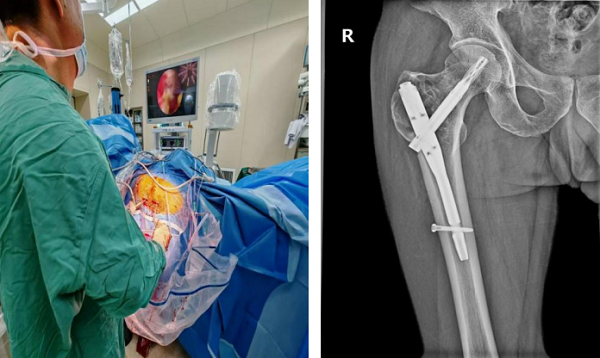

手术在全麻下开展,团队创新性采用关节镜辅助技术——通过关节镜的360°无死角视野,精准定位肿瘤病灶,借助专用器械彻底清除肿瘤组织;针对肿瘤较大导致的骨缺损,术中植入自体髂骨与人工骨混合骨材,并进行股骨近端内固定以恢复骨骼稳定性。

与传统手术相比,此次手术全程在关节镜监视下操作,不仅创伤更小,清晰观察瘤腔情况,还能通过低温等离子技术对残留肿瘤细胞进行灭活,有效降低复发风险,同时最大程度保护周围健康组织。